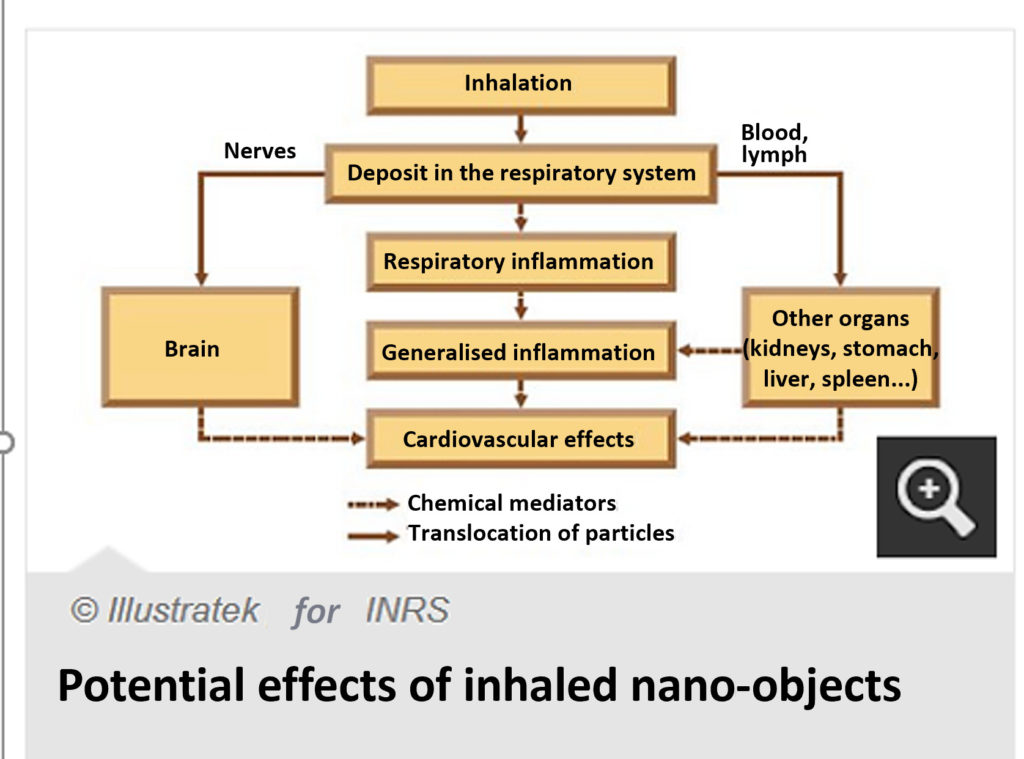

Deposition of particles along the respiratory tree is guided by their size. Particles between 10 nm and 100 nm are mainly distributed in the alveolar region.

After inhalation, some particles may migrate to:

- The blood

- The lymphatic system

- Brain structures

- The pleura

- Other viscera (liver, spleen)

The main effects are:

- Increased overall mortality

- Increased mortality from respiratory and cardiovascular causes

- Impairment of lung and heart function

- Pulmonary inflammatory effects

- Disruption of blood coagulation